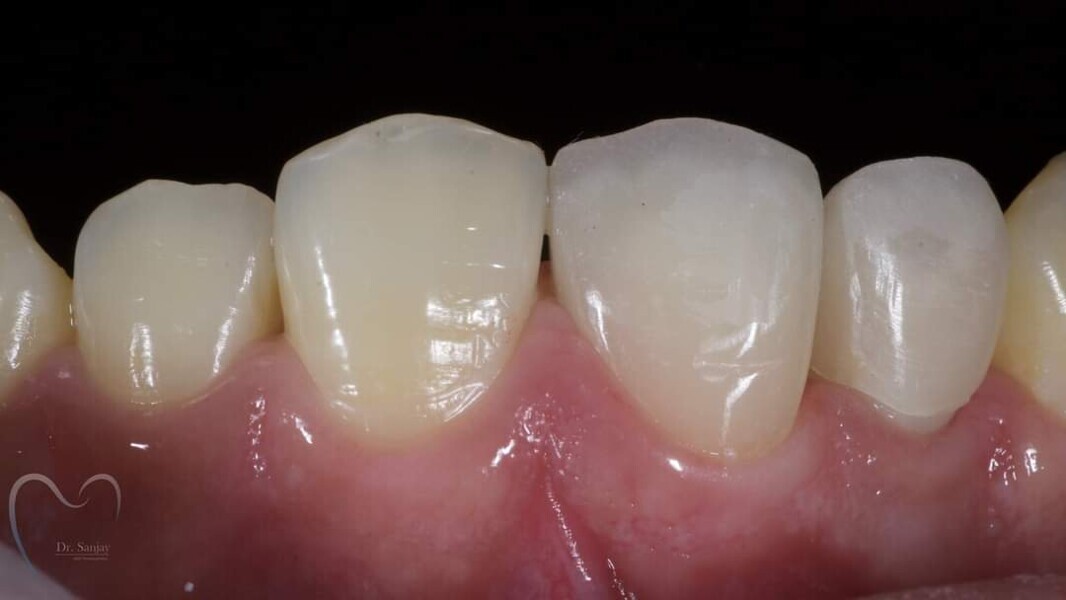

Esthetic Rehabilitation of Maxillary Anterior Teeth: Dr Sanjay Sah